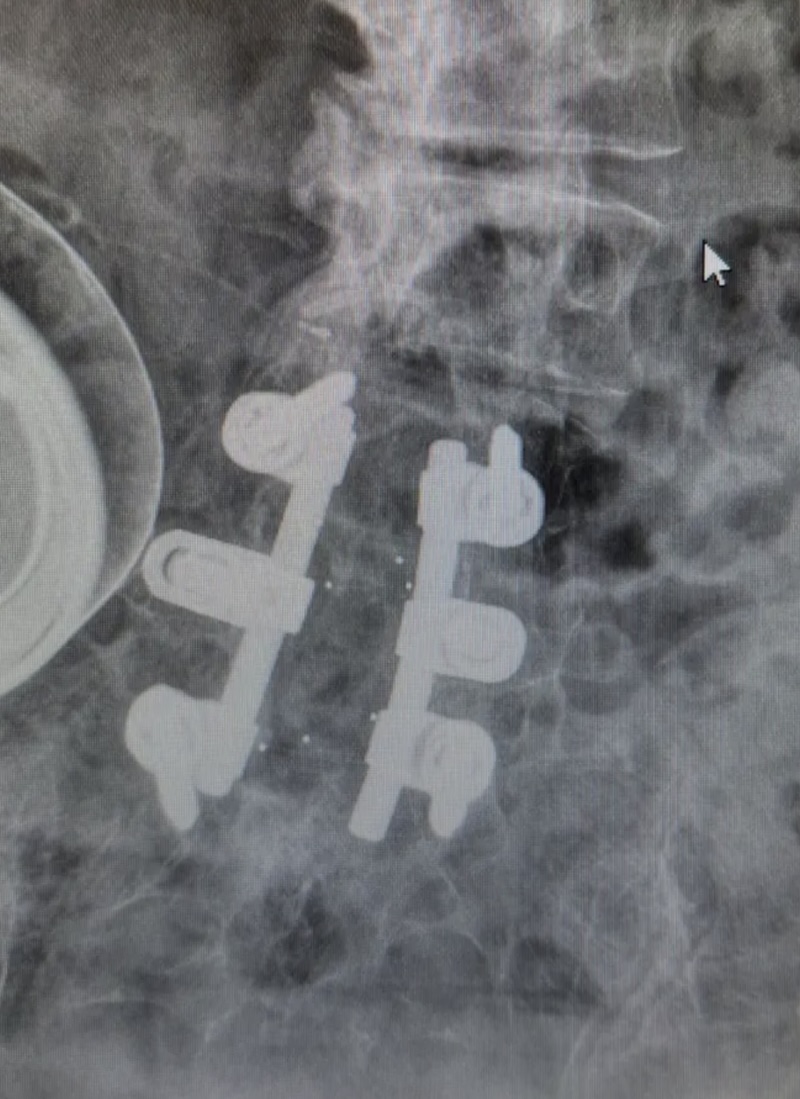

The MONARCH Spine System was originally produced by DePuy and is a titanium thoracolumbar pedicle screw fixation system. It is characterized by the pedicle screw with a polyaxial offset plate.

• Secured by 8mm (9/16 will work) Hexagonal nut

• Washer below hex nut

• Offset connector below washer

• Offset connector to rod is 2.5mm female hex nut